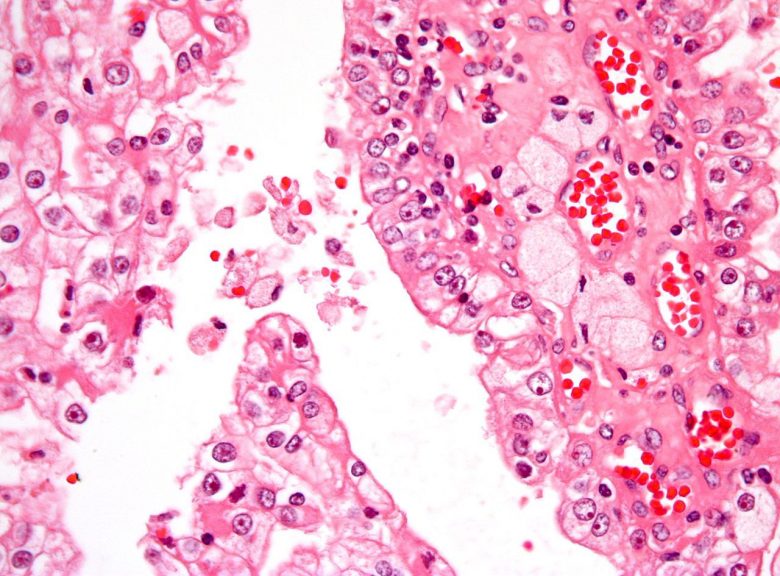

Image Credit: Nephron / Wikimedia Commons.

Anal cancer

“Anal cancer cases have been increasing over several decades. Infection with human papillomavirus (HPV) is the major risk factor for anal cancer.

“Signs of anal cancer include bleeding from the anus or rectum or a lump near the anus. Tests that examine the rectum and anus are used to detect (find) and diagnose anal cancer. Certain factors affect the prognosis (chance of recovery) and treatment options.”